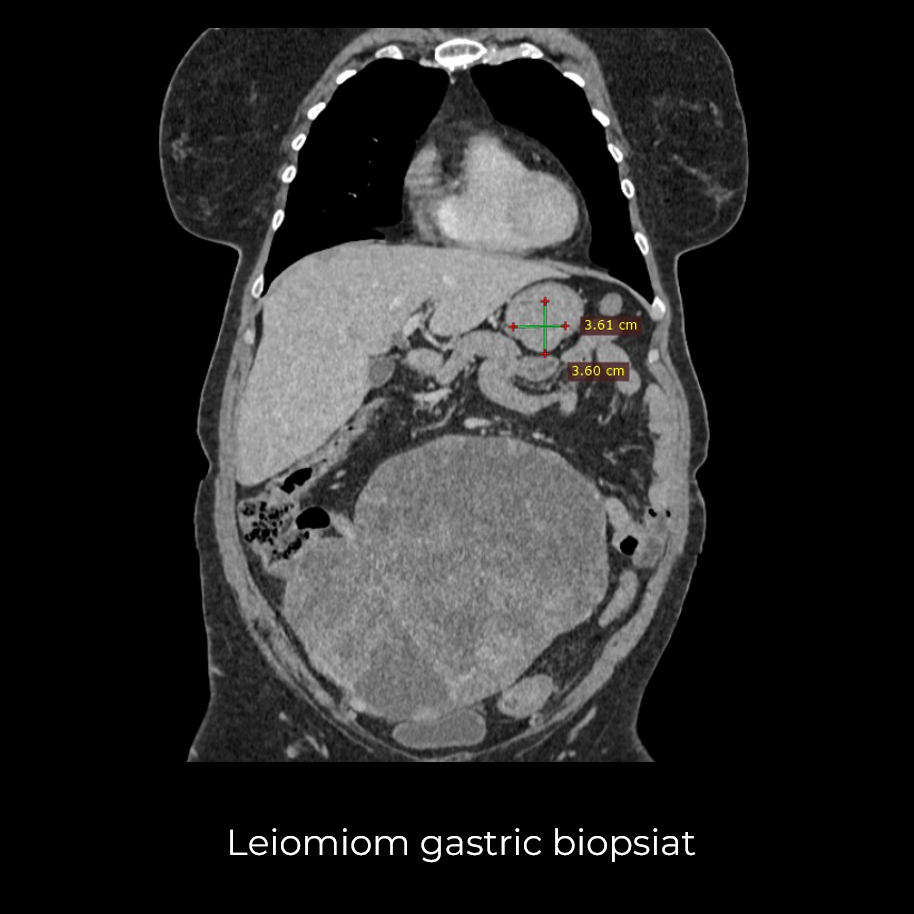

Uneori, o durere aparent banală ascunde în spate o realitate medicală mult mai serioasă. Așa s-a întâmplat și în cazul unei paciente de 63 de ani, care a ajuns la spital pentru dureri pelvine persistente. Investigația CT a schimbat însă complet perspectiva: au fost descoperite trei formațiuni tumorale în zone diferite ale corpului – o tumoră mamară stângă (carcinom mamar invaziv biopsiat), o tumoră pelvi-abdominală voluminoasă (tumoră ovariană) și o formațiune la nivelul peretelui posterior gastric (leiomiom gastric biopsiat).

- Gastrectomie segmentară – excizia porțiunii afectate din stomac